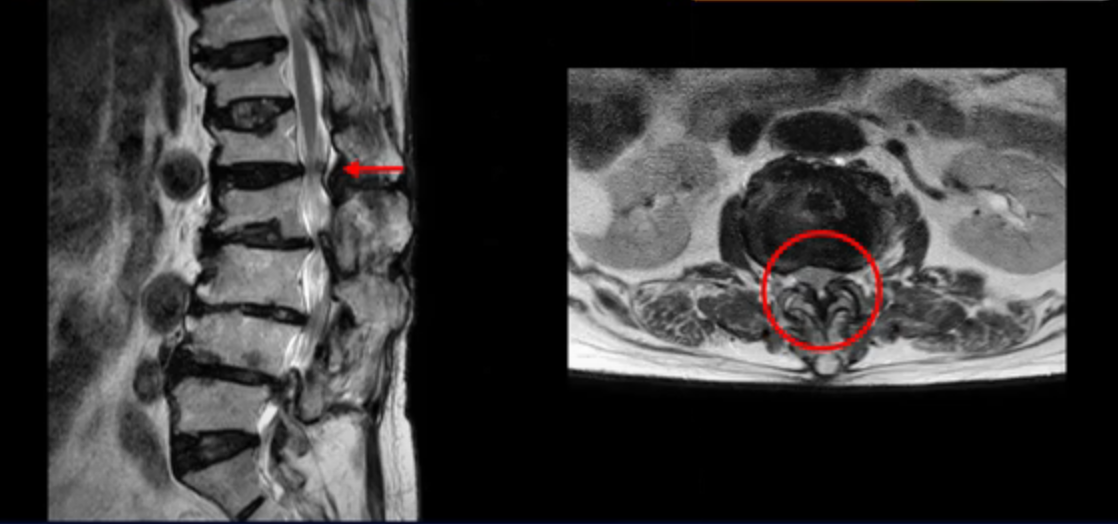

이 환자분은 허리 여러 마디가 다 안 좋아서 오랫동안 허리가 아프셨고 허리도 일찌감치 굽으셨습니다. MRI를 보시면 허리 여러 마디가 심하게 안 좋습니다.

보시다시피 4번 5번 마디에는 심한 중심성 협착이 있고

3번 4번에도 중심성 협착이 있습니다.

또 신경 가지가 빠져나가는 추간공도 좁아져 있습니다. 이런 이유로 환자분의 다리가 저리고 아픈 겁니다.

또한 척추뼈 여러 개가 압박 골절과 변형으로 찌그러져 있고

골다공증도 심하시고 보시다시피 근육량이 너무 적습니다. 근육이 정상적인 분들과 비교해보면 근육이 얼마나 적은지 알 수 있습니다.

이렇게 근육도 적고 뼈가 약하신 분들 게다가 여러 마디가 안 좋은 분들은 수술하면 결과가 안 좋을 가능성이 매우 높습니다. 그래서 지방의 척추 병원과 서울의 한 최상급 대학병원에서도 수술을 안 받는 게 좋다, 수술한다 해도 위나 아래가 무너질 수 있다고 들으셨습니다.